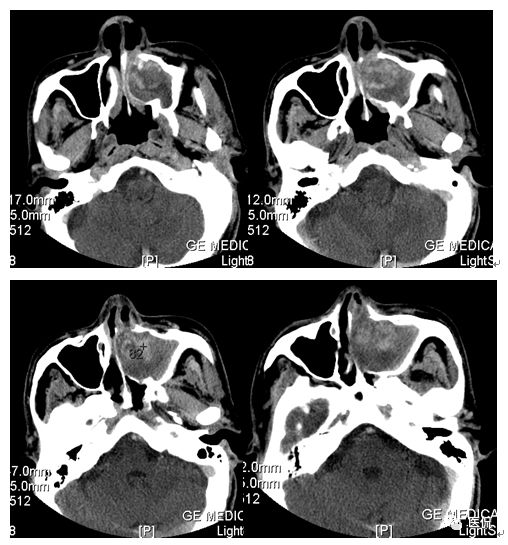

冠状位平扫

CT平扫及增强示:左侧上颌窦及鼻腔可见软组织密度影,呈膨胀性生长,周围骨质压迫性吸收破坏,累及左眶,病灶密度不均匀,周边区可见点状钙化,增动脉期轻度强化,局部见小灶性稍高密度区,静脉期病灶内见不均匀明显强化,CT值最高达117HU,延迟期强化范围有所增大。